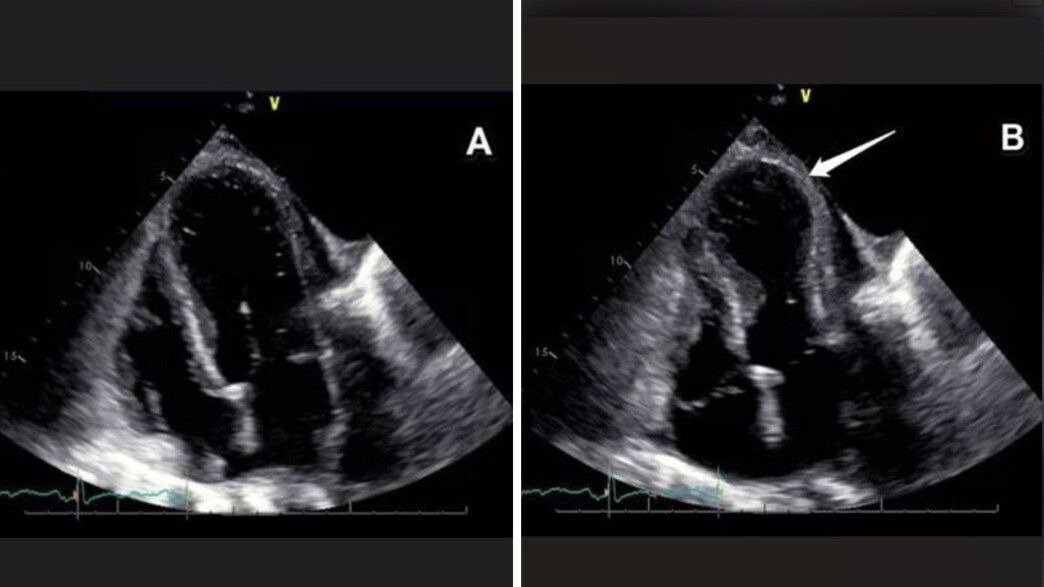

هكذا يبدو “القلب المكسور”:

في الصورة على اليسار نرى القلب في حالة الارتخاء (الانبساط – دياستول)،

أما في الصورة على اليمين فنرى القلب في حالة الانقباض (الانقباض – سيستول)، حيث ينقبض فقط الجزء القاعدي من القلب بينما يبقى الطرف (القمة) مرتخيًا، ما يمنحه مظهرًا يشبه البالون، دون أن ينقبض هو أيضًا، ولذلك تُسمّى هذه الظاهرة انتفاخ القمة (Apical Ballooning)

تشرح الدكتورة جُمّانة إسبنيولي أسعد، أخصائية أمراض القلب في المركز الطبي لين التابع لكلاليت – لواء حيفا والجليل الغربي، ظاهرة ازدادت نسبة انتشارها خلال العامين الأخيرين: “أوضح مثال على تأثير المشاعر في الجسد هو متلازمة تاكوتسوبو (Takotsubo cardiomyopathy)، المعروفة باسم ‘متلازمة القلب المكسور’. وهي حالة حادة وقابلة للعكس، تتمثل في ضعف مفاجئ في وظيفة البطين الأيسر للقلب، تحدث نتيجة ضغط نفسي شديد، كالفقدان، الانفصال، الخوف الشديد أو حتى الفرح المفاجئ”. وتشير إلى أن الخصائص الطبية لهذه الحالة تُشبه أعراض النوبة القلبية: “يصل المريض وهو يعاني من ألم في الصدر، ضيق في التنفس، تغيّرات في تخطيط القلب (تشبه احتشاءً حادًا – STEMI)، وارتفاع في إنزيمات القلب (التروبونين). وفي فحص الإيكو، يظهر نمط مميز يتمثل في توسّع وعدم انقباض قمة القلب (الأبكس)، ما يعطيها شكل بالون (Ballooning)”. وتضيف: “المفاجأة تظهر خلال القسطرة القلبية، إذ رغم الأعراض الدراماتيكية تكون الشرايين التاجية سليمة تمامًا. ويُرجّح أن السبب يعود إلى اندفاع مفاجئ ومفرط لهرمونات التوتر، مثل الأدرينالين، التي تؤثر مباشرة على عضلة القلب”.